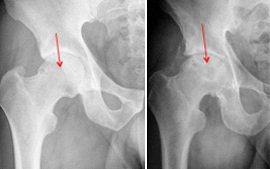

Na displasia da anca ou doença displásica da anca (DDA) o acetábulo é oblíquo, pouco profundo, estreito, lateralizado, antevertido e com deficiente cobertura anterosuperior.

O fémur tem cabeça pequena, colo curto, anteversão exagerada do colo, ângulo cervicofiafisário aumentado, desvio posterior do grande trocanter, canal femoral estreito.

OS EXAMES MAIS ÚTEIS PARA O DIAGNÓSTICO, são:

RX: face correcta da bacia, Rx de face e perfil das ancas

TAC

RMN (com ou sem gadolineo)

Quando houver sintomatologia (dor, claudicação) e alterações imagiológicas há indicação para cirurgia, para correção do valgo e para melhorar a congruência articular, diminuindo a sintomatologia e melhorando o bem-estar e qualidade de vida do paciente, e prevenindo a evolução e instalação da artrose grave.

A cirurgia deverá ser feita antes que haja artrose avançada.